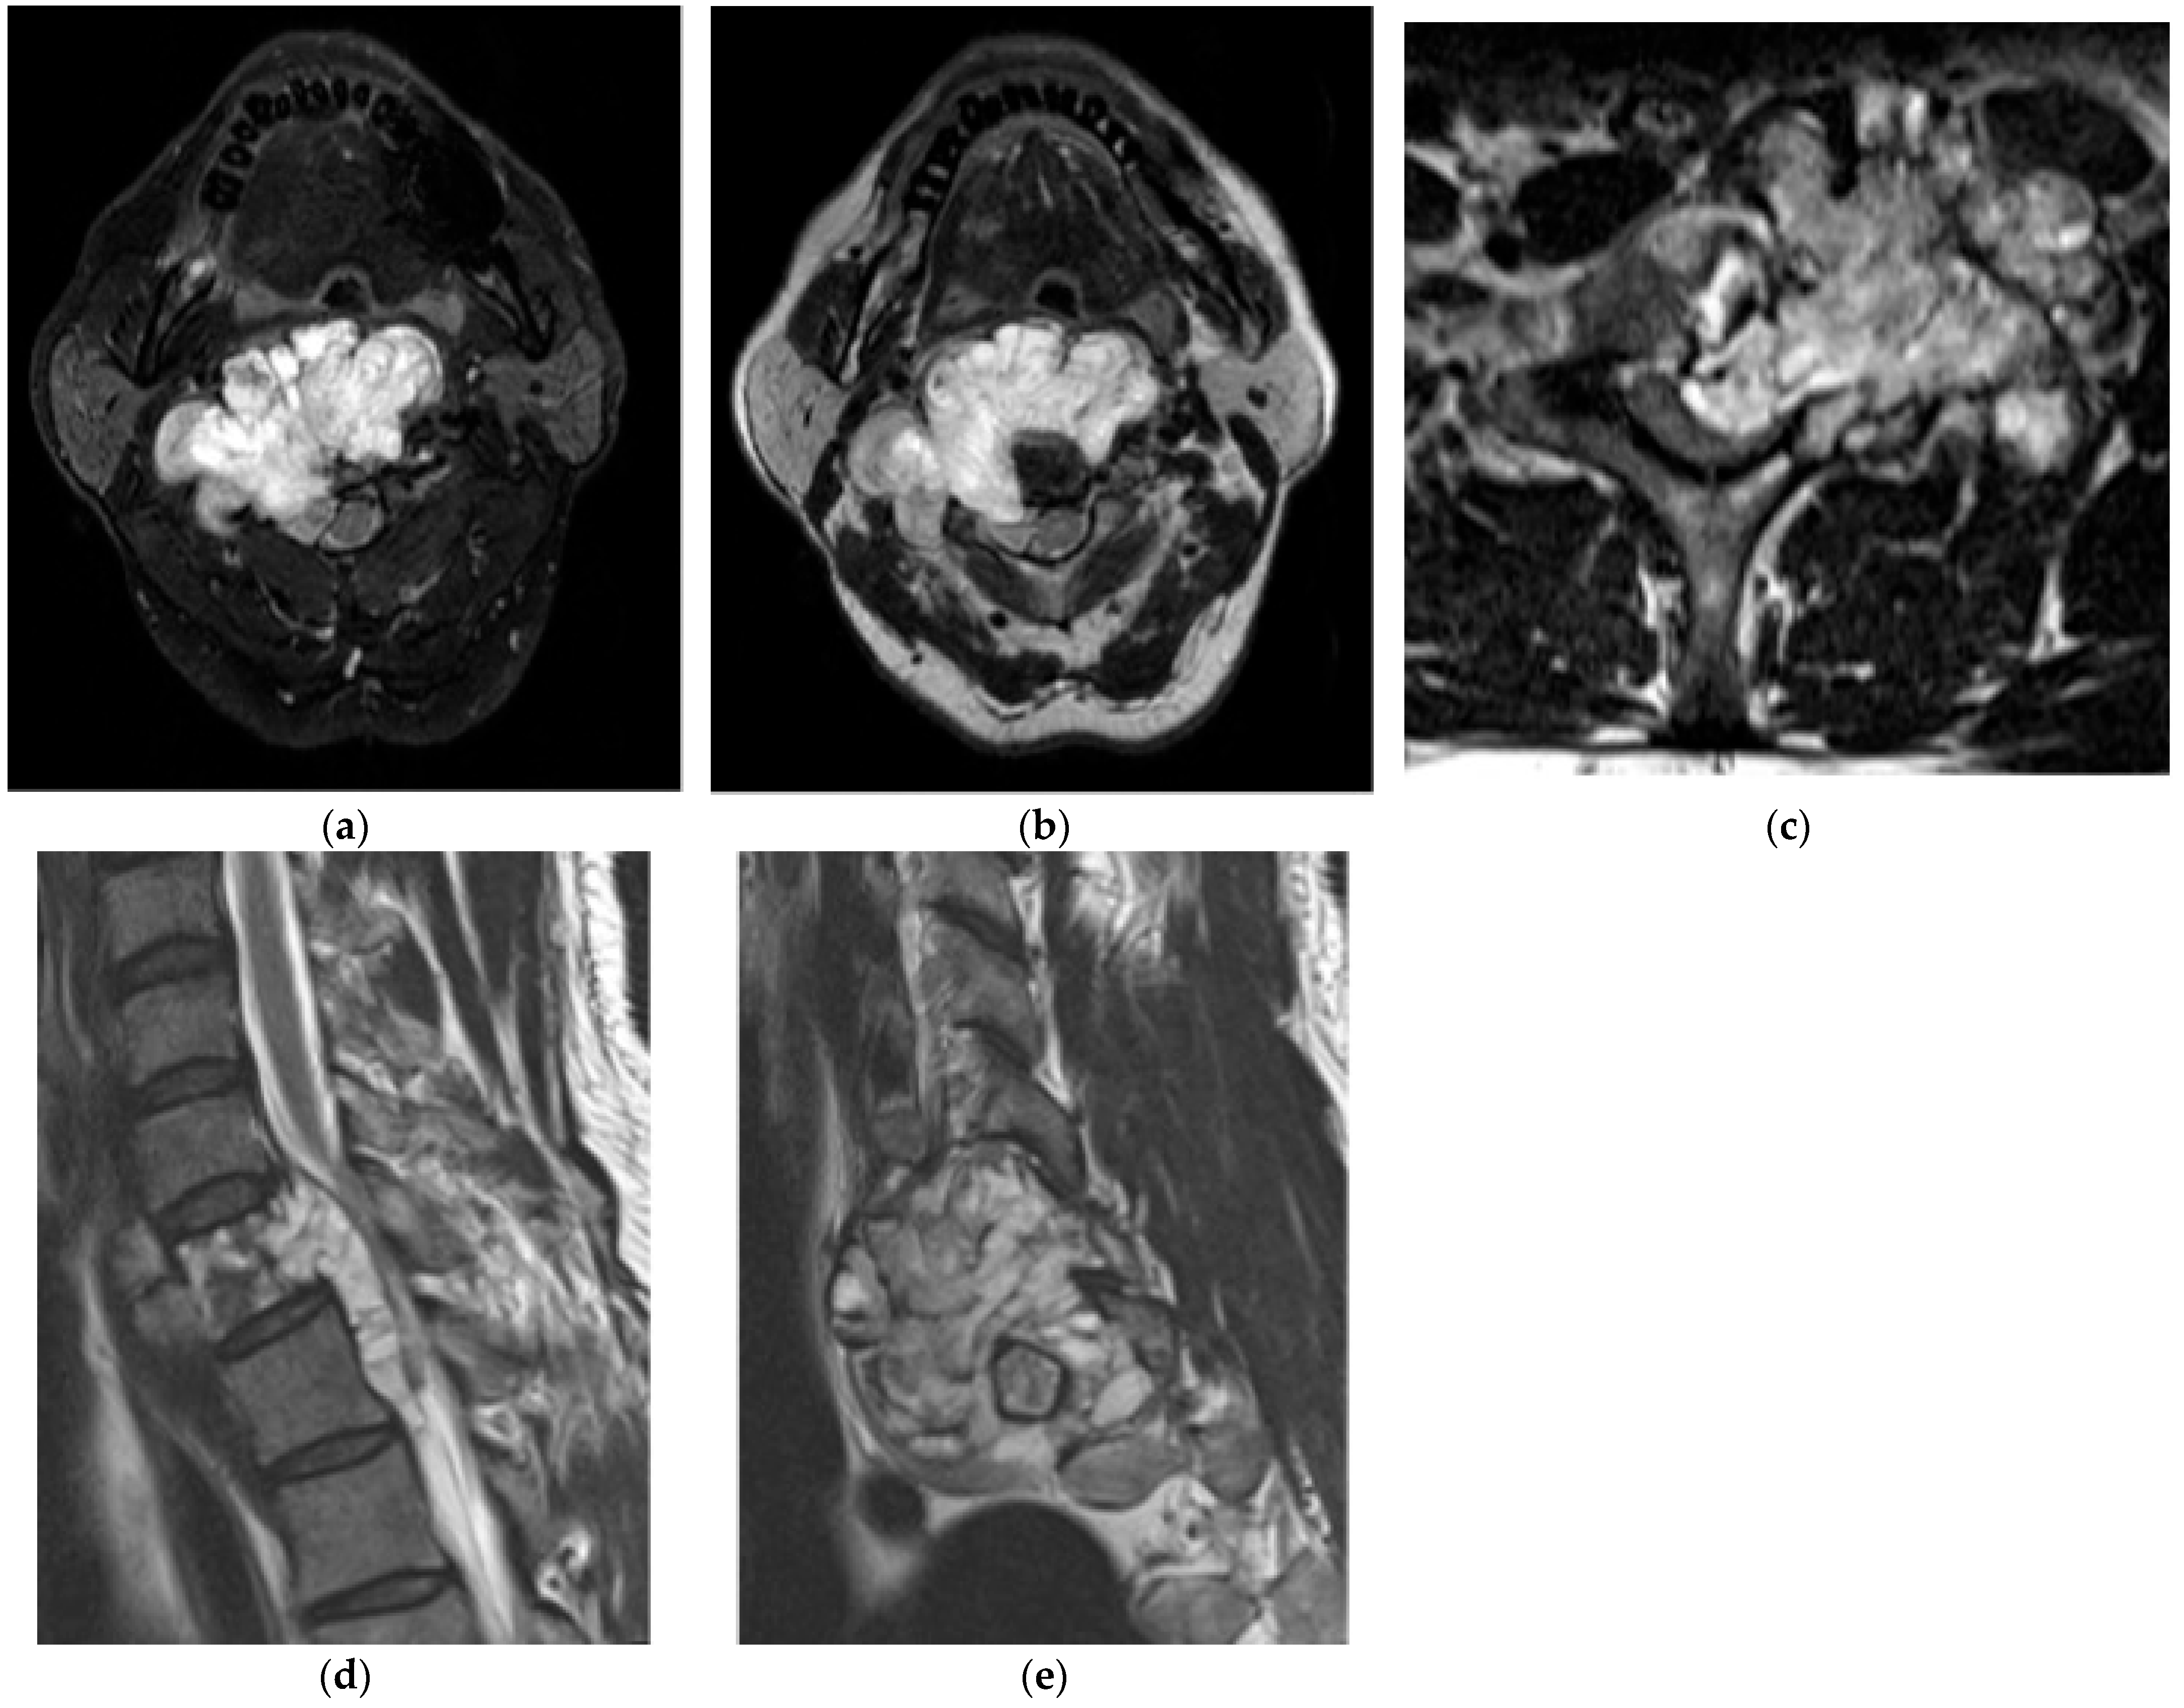

2.5.2. Aneurysmal Bone Cyst